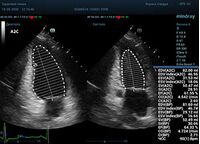

Таким образом программный алгоритм может упростить задачу опытного доктора, экономя его время на настройку допплеровских режимов. Mindray Resona может выступать и в качестве «учителя» для докторов-новичков, показывая примеры правильной работы в процессе оптимизации.

Что могут предложить современные приборы? Приборы нашего времени являются мощными вычислительными машинами, способными обрабатывать полученную информацию даже без помощи человека. Система автоматического вычисления фракции выброса – AUTO EF на приборах серии Resona компании Mindray сделает все за вас. За пару секунд прибор сам отыщет нужную фазу сердечного цикла и произведёт измерение и расчеты, а также покажет график изменения объема в сердечном цикле. От Вас требуется только получить качественное 4С и 2С сечение. Впрочем, прибор всегда оставляет возможность коррекции, если доктор имеет свое мнение на расположение точек планиметрии или момента измерения по ЭКГ каналу.